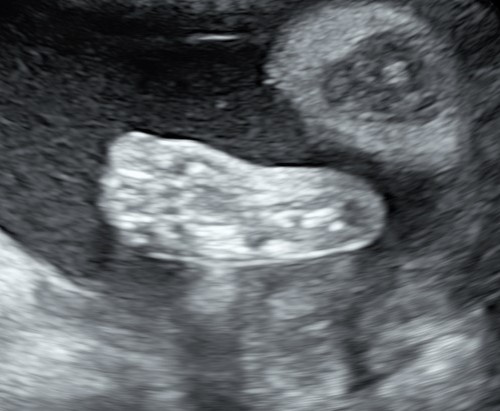

Il tesoro in ecografia è sempre più bello, infatti è da questo mese, ma soprattutto dal prossimo che comincerà ad ingrassare e diventare più tondetto per la gioia degli occhi di babbo e mamma!